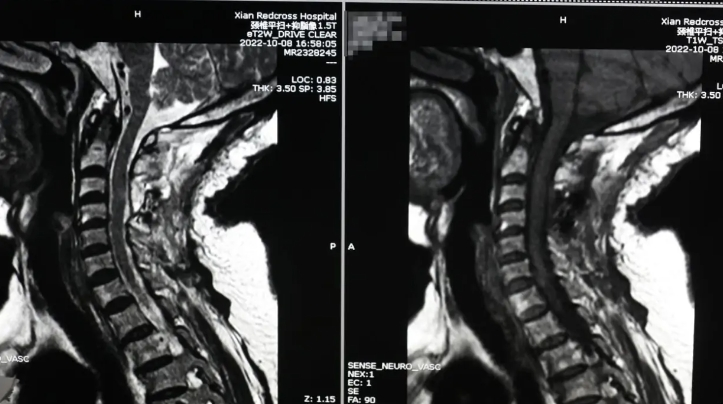

经过术前讨论和完善的准备,杨俊松医生为患者完成颈椎管内肿瘤切除。手术将肿瘤全部切除,并没有对周围脊髓组织造成丝毫损伤,术中椎板回植,确保切除肿瘤的同时保留颈椎本来结构。

术后:肿瘤完整切除、脊髓神经无损伤

一年来,患者按时随访,没有出现任何异常。术后一年查体显示患者可以正常前屈后伸,颈椎活动度正常,复查影像资料显示,肿瘤完全切除,脊髓减压彻底,内固定良好,脊柱稳定性无异常。

内固定在位、脊柱稳定性良好